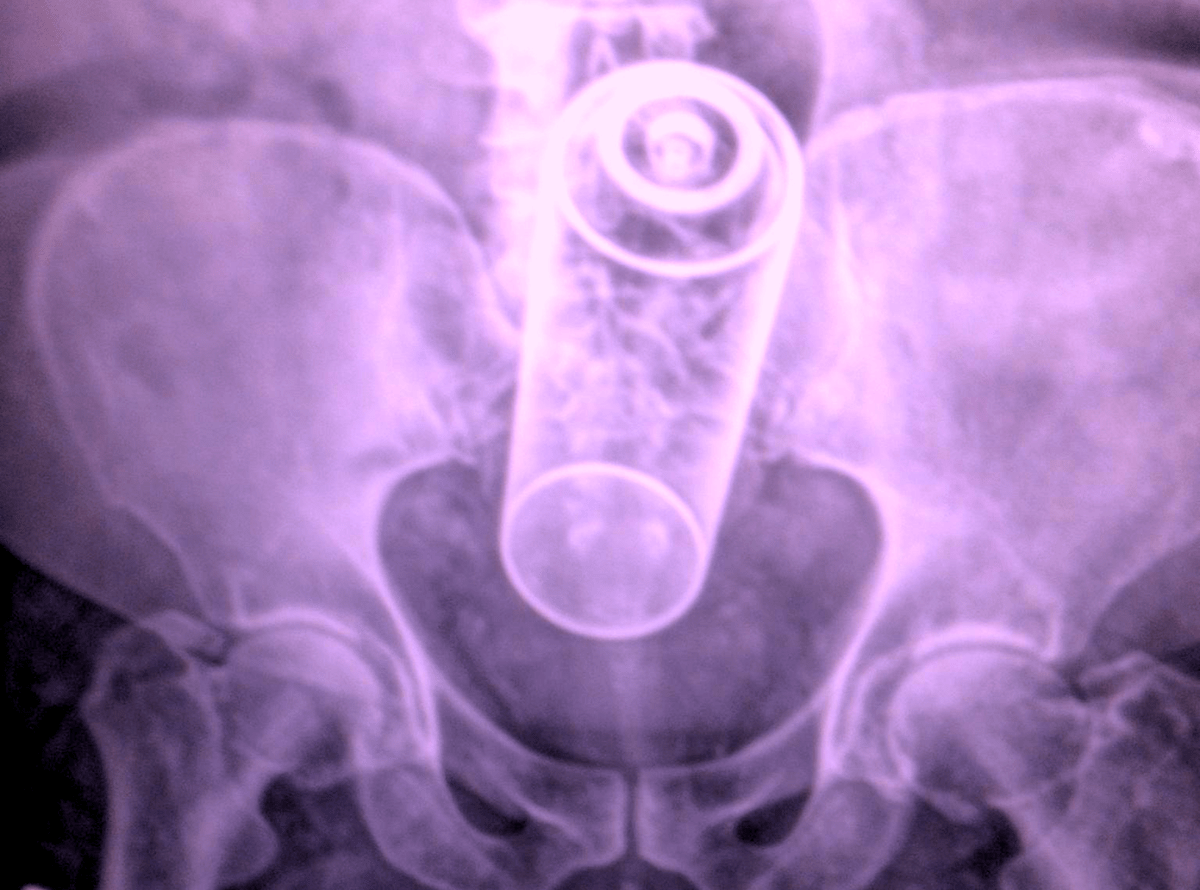

Science Explains Why People Stick Foreign Objects Up Their Butts . But the data, of course, also reveal that some of those foreign bodies were introduced on purpose .

According to ER doctors, getting foreign objects stuck in your anus is surprisingly common . Something tells us that they didn't really slip and "fall" onto these objects!